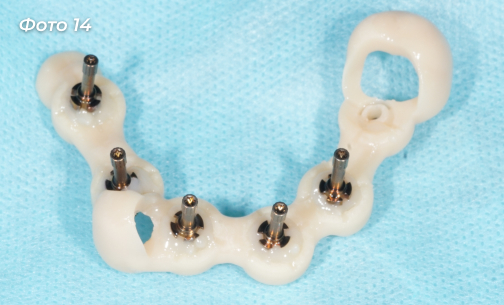

Через 4 месяца после первой операции было проведено оперативное вмешательство на нижней челюсти. Была выбрана другая тактика, были удалены сразу все зубы (Фото 11).  Установлено 6 имплантов  (Фото 12) по хирургическому шаблону  (Фото 13).

Изготовлена и установлена временная конструкция на нижнюю челюсть (Фото 14, 15).